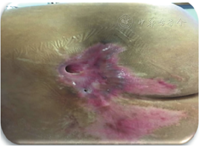

2.局部创面评估。依据国际创伤最新伤口评估三角理论[8]对创面伤口床、伤口边缘、周围皮肤三方面进行全面评估:创面伤口床基底呈现75%黄色、25%红色,均为不健康组织,且全层皮肤缺失、筋膜肌肉均已暴露,为4期压疮[6];测量长×宽×深虽然只有7 cm×8 cm×3 cm,但存在2个巨大腔洞,使用钟表法记录:10点至2点方向存在深达8.3 cm的巨大潜行,1/2止血钳已完全没入、9点方向存在深4.3cm窦道、创面实际深度远超表面所见;渗出液大量清亮黄色,伴刺激性气味。伤口边缘呈明显内卷状态。周围皮肤浸渍明显、皮肤菲薄。见图1。